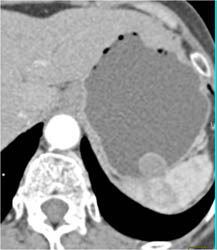

Diagnosis

Intrathoracic Stomach